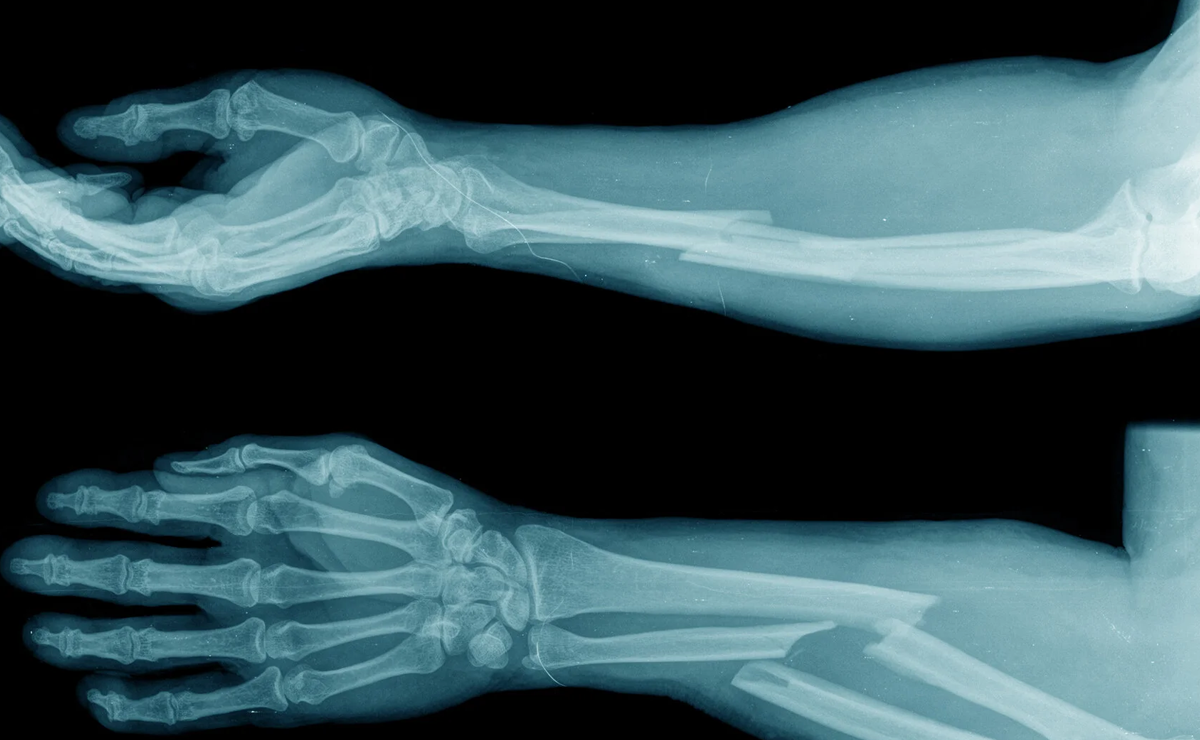

Orthopaedic trauma deals with fractures and injuries resulting from accidents, falls, sports injuries, or high-impact trauma. Fractures can involve bones of the upper or lower limbs, pelvis, or spine and may range from simple cracks to complex, displaced injuries. Prompt and accurate treatment is essential to restore normal bone alignment and function.

Treatment options depend on the type and severity of the fracture and may include casting, splinting, or surgical fixation using plates, screws, rods, or external fixators. Early mobilization and rehabilitation play a vital role in recovery, helping patients regain strength and movement while preventing stiffness and complications. Comprehensive trauma care ensures proper healing and a safe return to daily activities.